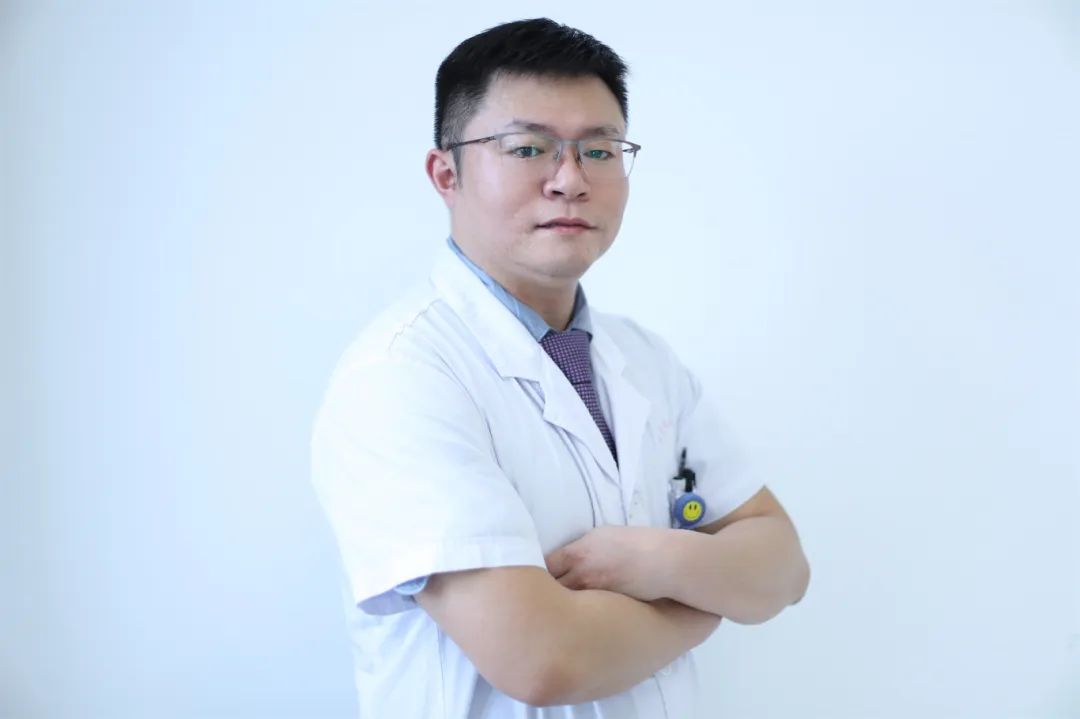

福建三博福能脑科医院骨科与神经康复科主任张朋,正是刀尖上的“优秀舞者”,毫厘之间,用穿刺针与柳叶刀解救众多患者于病痛折磨中。

“如履薄冰 如临深渊”八个大字,牢牢固定在该院骨科与神经康复科的办公室墙面上,警醒每日来往的医护人员,这也是张朋副主任医师日常工作的真实写照。

张朋主任手术中。

张朋:副主任医师、神经医学在读博士、福建三博福能脑科医院骨科与神经康复科主任。

专业特长:擅长三叉神经痛、颈椎病、腰椎间盘突出、椎管内肿瘤、脊髓内肿瘤及脊髓栓系、脊髓脊膜膨出、脊柱裂、脊柱源性疼痛(盘源性腰痛、腰肌劳损、骨质疏松性椎体压缩骨折等)、周围神经卡压、四肢关节及骨质疏松性骨折等疾病的诊疗。